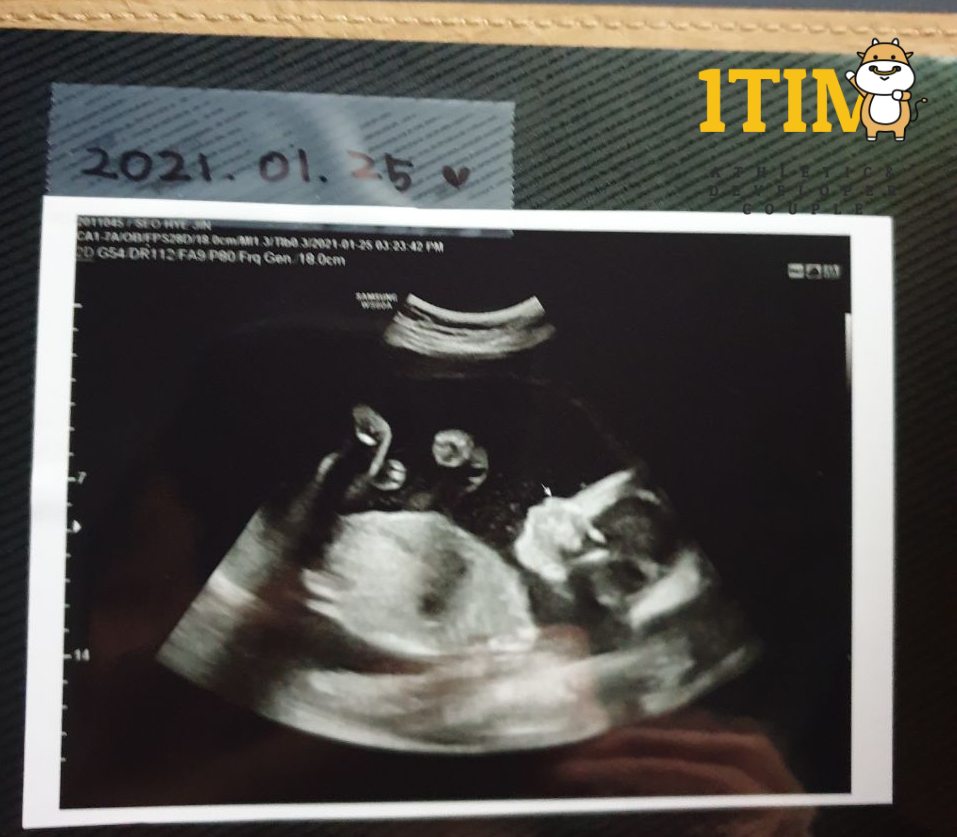

2021. 1. 25. (21주 4일)

오늘은 한달만에 정기검진이 있는날. 정밀 초음파가 예정되어 있다.

양손가락/양발가락 갯수, 양쪽 귀, 입술, 코가 잘~~~ 붙어있는지 확인했다.

물론 정상 ~ 키키키 대견하구나.. 크롱군..

태아 몸무게 : 460g (21w4d)

이제는 키 대신 몸무게와 머리둘레로 태아의 성장을 확인하는 시기